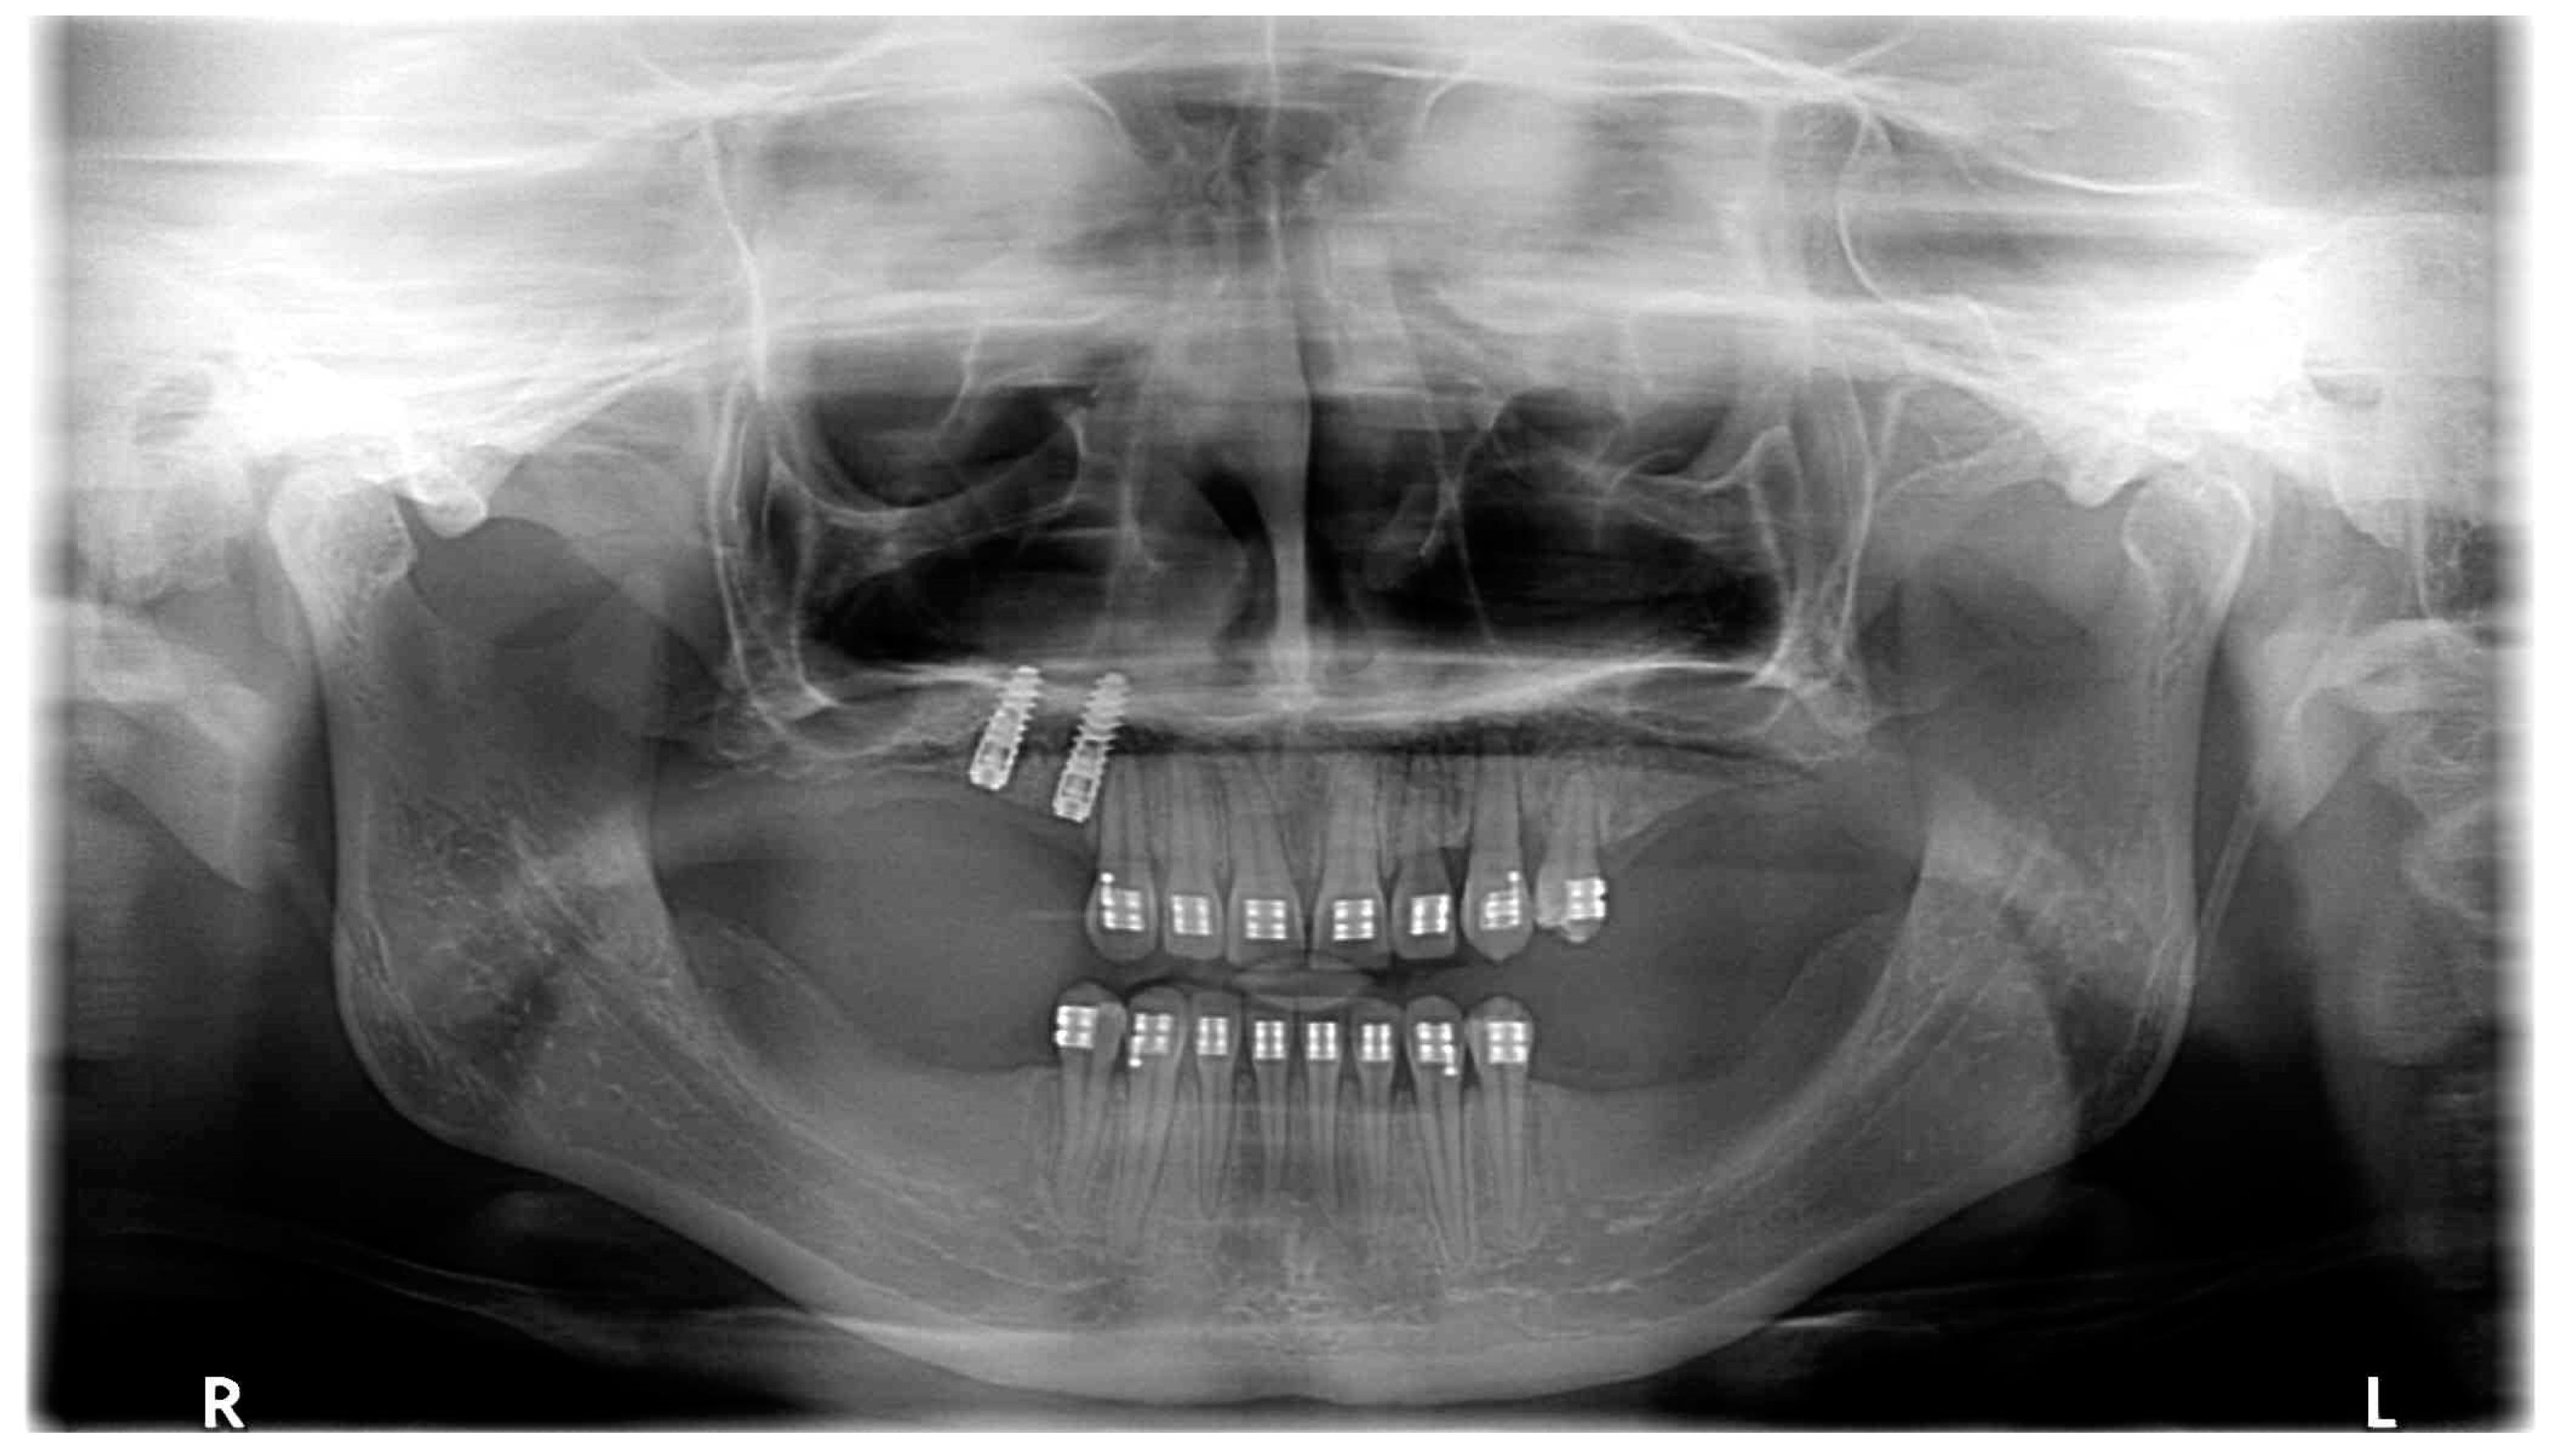

| March 2020 | The correct position of UL3; tooth no. 24 showed significant mobility; control panoramic X-ray: root resorption of tooth no. 24 (Figure 7); no possibility to conduct control visits on a regular basis due to COVID-19 pandemic—next appointment took place in November 2020. |